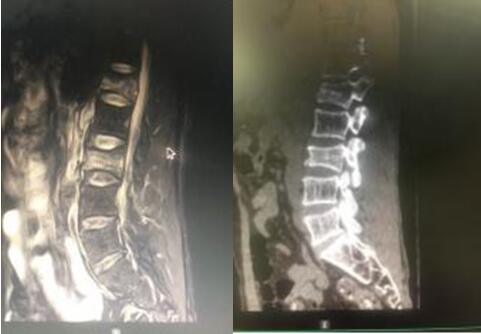

7月9日,經(jīng)與患者及其家屬充分溝通后,在脊柱外科蘇光輝主任、汪向東副主任帶領(lǐng)下順利進行了經(jīng)皮跨傷椎長節(jié)段后路內(nèi)固定手術(shù)治療腰椎骨折。術(shù)后傷口小、出血量極小約50ml,術(shù)后1周即可下地行走,患者及其家屬對手術(shù)效果相當滿意。

術(shù)后